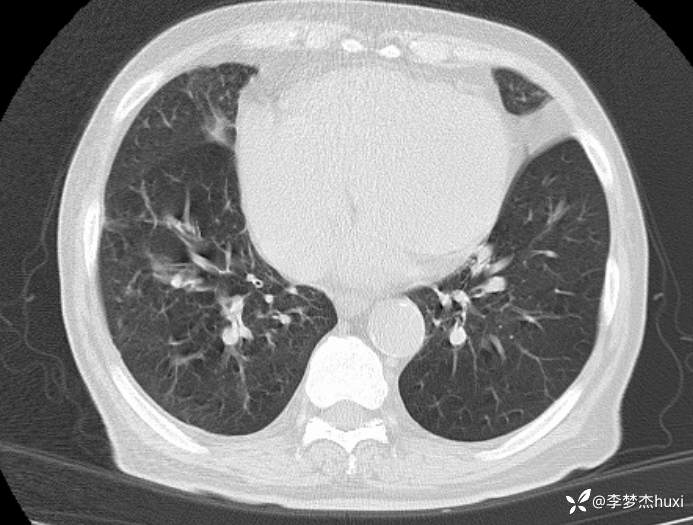

男, 82 岁,主因慢性咳喘20余年,患慢阻肺,平时喘息药物维持,半年前反复住院,并因为病重转上级医院治疗,自诉回家后做梦梦到自己换了一个狗肺,感觉从此不再喘息。